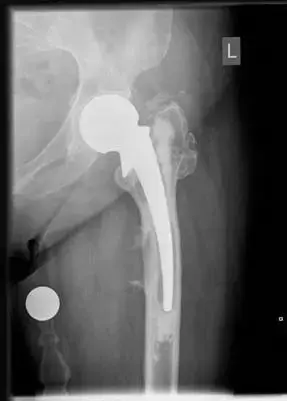

صورة توضيحية لـ مضاعفات استبدال مفصل الورك: التخلخل والالتهاب في صنعاء | د. محمد هطيف

مفصل الورك الاصطناعي المزروع

في جراحة استبدال مفصل الورك، يتم استبدال الأجزاء المتضررة من المفصل الطبيعي بمكونات اصطناعية:

* الساق الفخذية (Femoral Stem): يتم إدخالها في قناة عظم الفخذ.

* رأس كروي (Femoral Head): يُثبت على الساق الفخذية، وقد يكون مصنوعاً من المعدن أو السيراميك.

* الكوب الحقي (Acetabular Cup): يُزرع في عظم الحوض ليحل محل الحق الطبيعي.

* البطانة (Liner): تُثبت داخل الكوب الحقي، وتكون عادةً من البولي إيثيلين، السيراميك، أو المعدن، وتوفر سطحاً ناعماً ليتفصل مع الرأس الكروي.

تُصمم هذه المكونات لتعمل معاً بسلاسة، محاكية لوظيفة المفصل الطبيعي. تثبت هذه المكونات إما باستخدام ملاط عظمي (cemented) أو بطريقة غير ملاطية (uncemented) حيث ينمو العظم الطبيعي داخل سطح المفصل الاصطناعي الخشن.